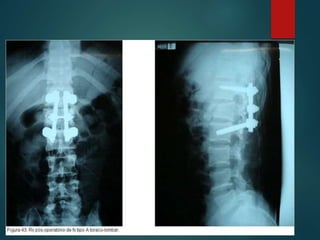

 Antero-posterior e perfil de toda

a coluna 3% a 5% apresentam

fraturas múltiplas.

 Avaliação AP:

 Craniocaudal, deslocamentos,

angulação, ↑ ou ↓ do corpo

vertebral, ↑ interpedicular,

alinhamento proc espinhoso,

integridade da lamina e

processos transverso.

 Avaliação perfil:

 Deslocamentos ant-post, ↓ do

disco, cont da junção lamina-

pedículo-corpo, curvaturas.